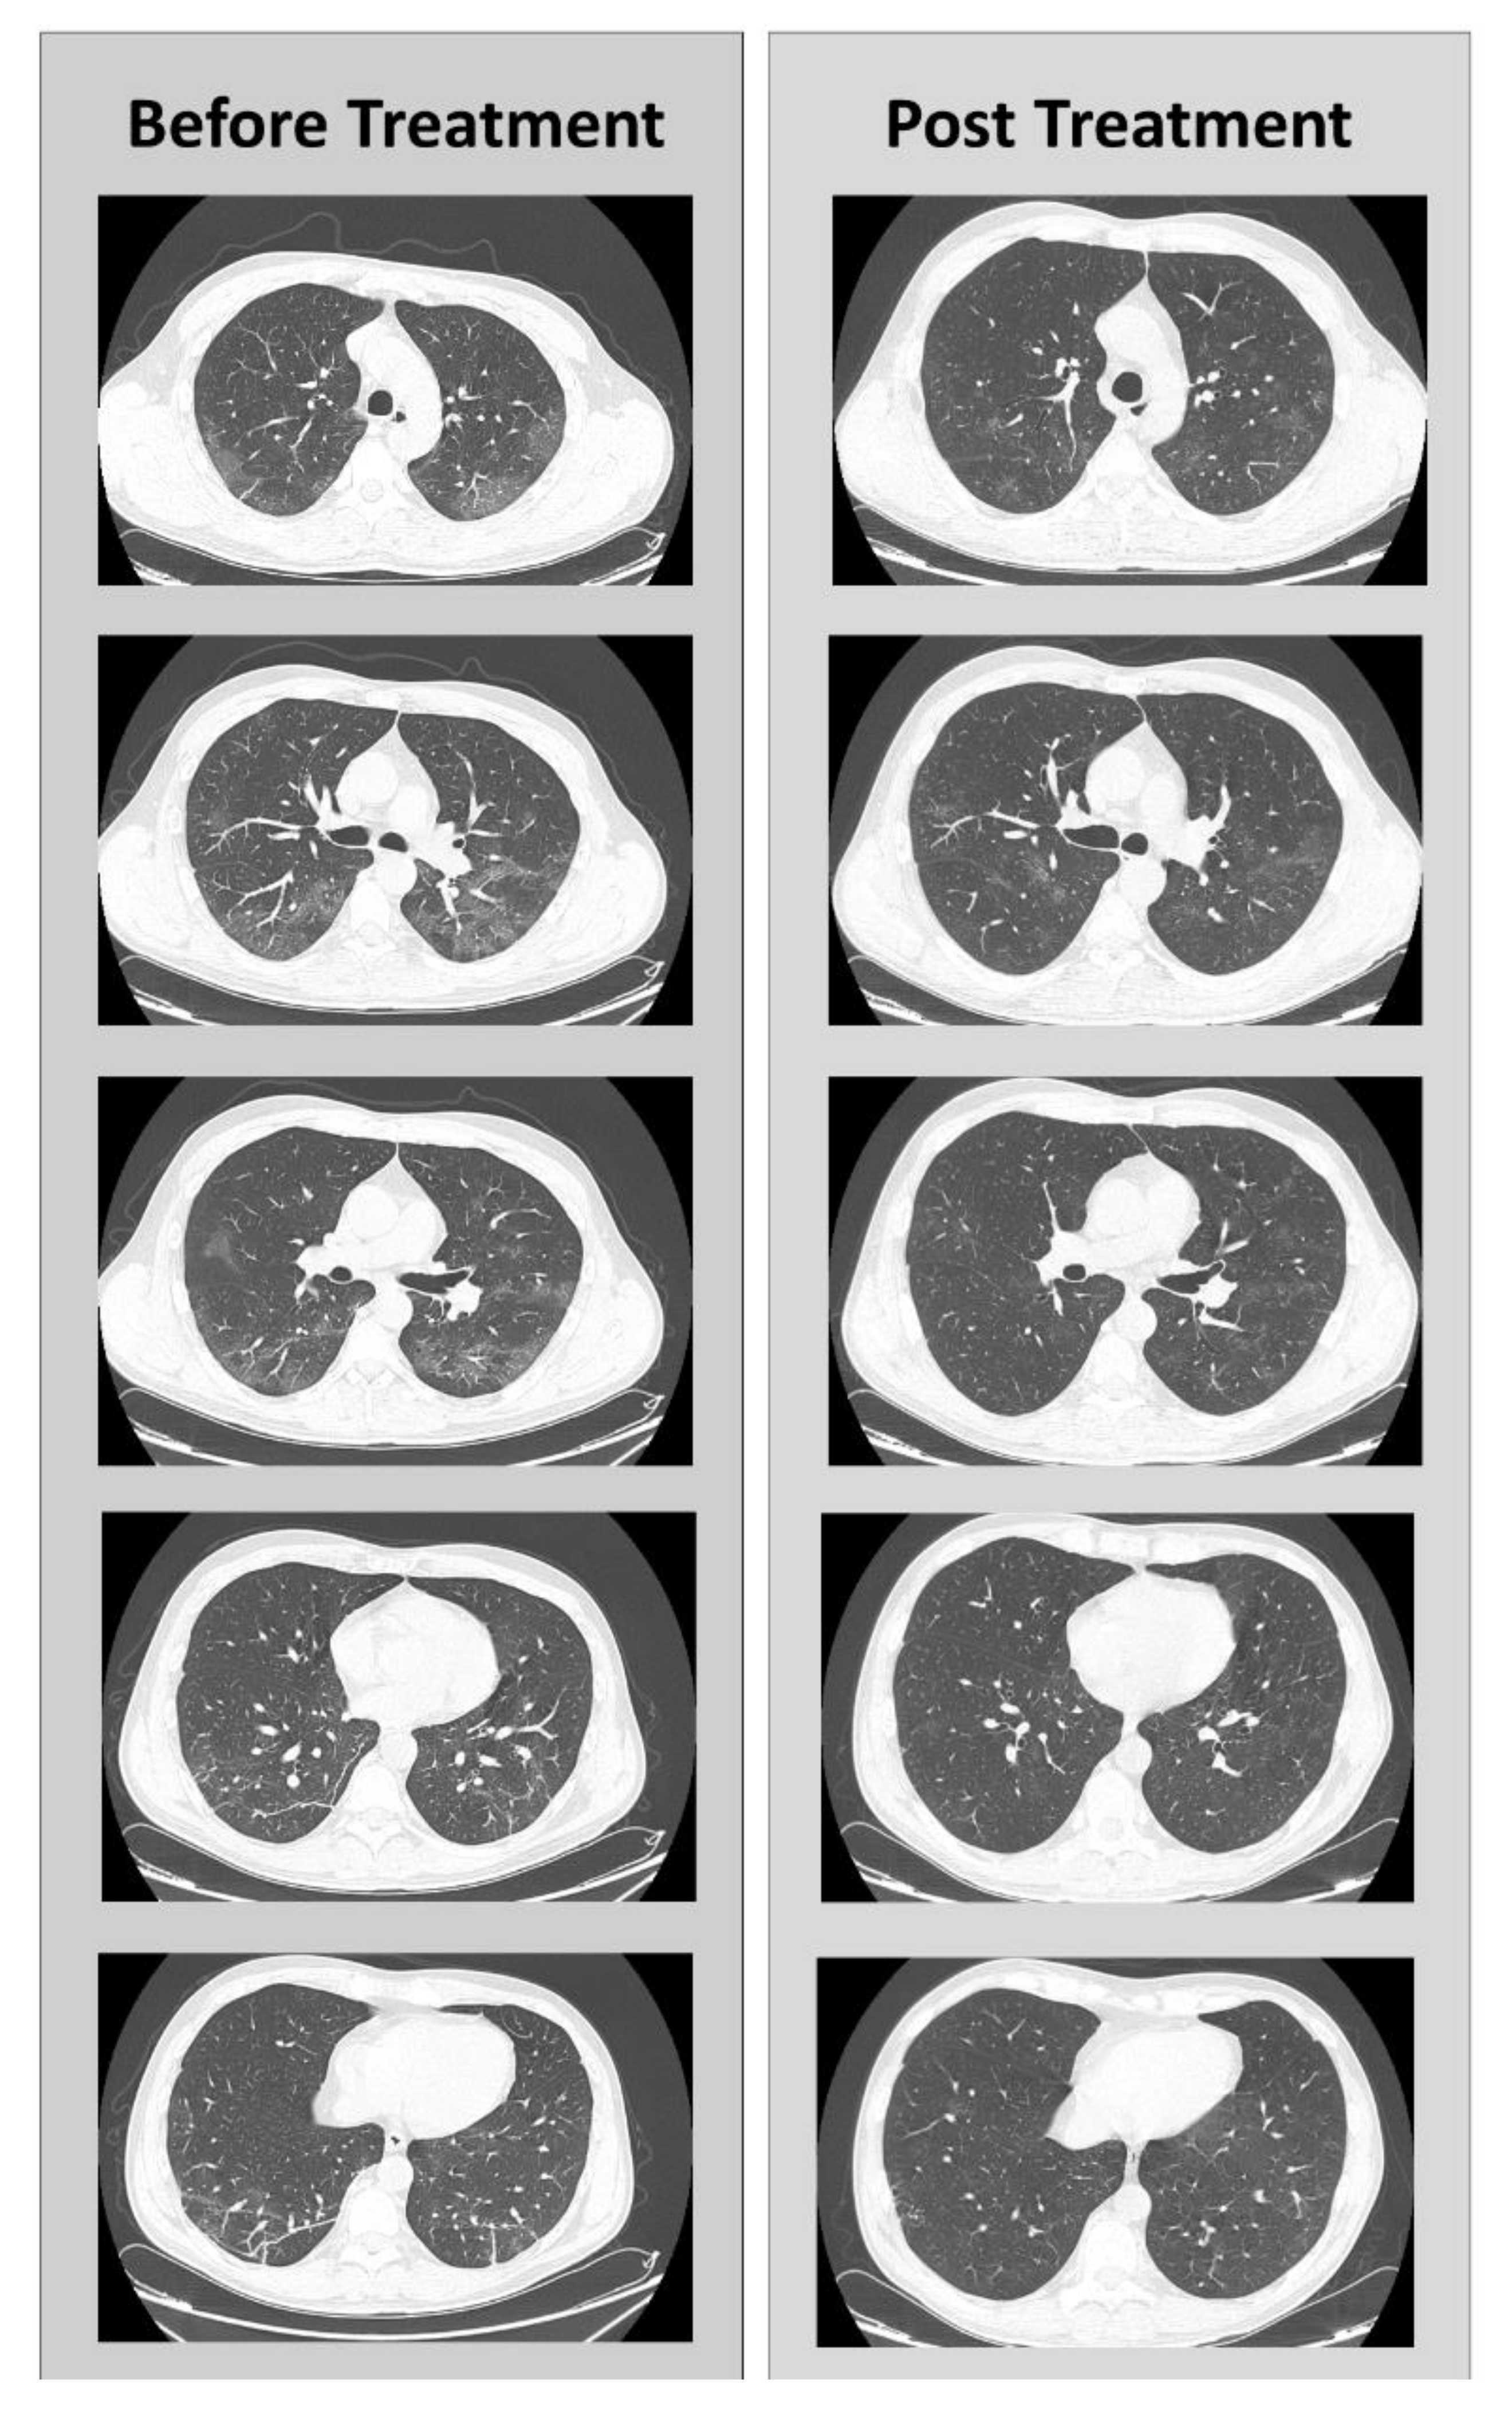

Finally, in the high-resolution CT-scan on April 20, a reduction in the ground-glass opacities, only appreciated in the antero-medial segment of the RUL, and a reduction of visceral pleural thickening lesions were observed. Pleuroparenchial fibrosis was no longer detectable, and there was only one residue to the right of a thin pleuroparenchymal stria with millimetric fibrotic pseudonodules. The picture appeared to be significantly improved compared with the previous CT-scans (Figure 2).

Figure 2.

Comparison of CT scans before and after adenosine treatment, in different sections.